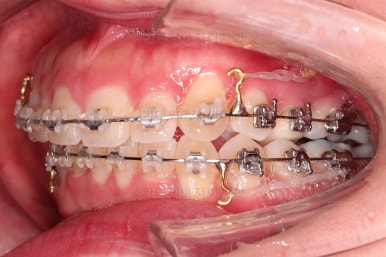

앞에서 봤을 때 치열은 가지런해졌지만 기울어진 느낌을 조금이라도 잡아보고자 미니스크류를 이용해서 입매 개선 및 기울기 개선을 시도했습니다.

미니스크류가 구성되었고요.

기울기와 돌출입을 개선하고자 이러저리 밀고당고 하는 모습입니다.

오히려 이전 사진보다 치열이 더 틀어지고 잘 안맞는 모습이죠?

환자분도 이때부터는 매우 힘들어하시긴 합니다.

괜히 잘 맞아보이는 걸 손대서 이상해지는 느낌일거거든요.

잘 설명 드려가면서 좀 더 좀 더 진행해 봅니다.